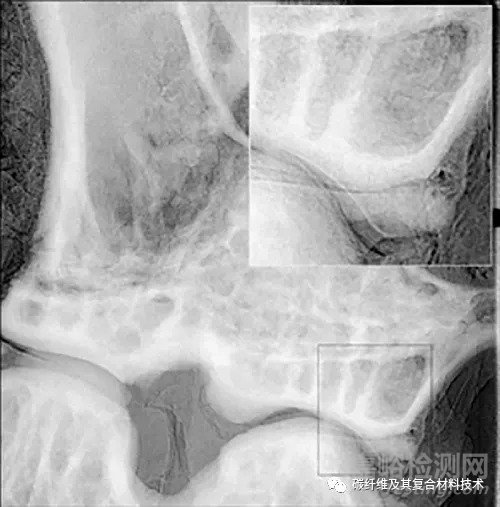

使用inCiTe系統(tǒng),可以高對比度可視化組織,例如在下面顯示的小鼠樣品膝蓋情況(圖1),從而可以詳細檢查軟骨。下圖(圖2)所示的復合材料中的芳綸纖維Kevlar,借助相襯成像,可以在材料中看到尺寸為10-20μm的單根纖維。

圖1小鼠膝蓋軟骨的高對比度圖像